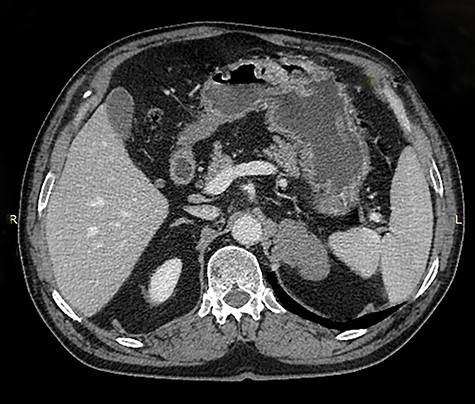

Because of its relatively large size and the patient’s request, he underwent a laparoscopic transperitoneal left adrenalectomy in the right lateral decubitus position (two 10-mm and one 5-mm ports). Intraoperatively, an enlarged left adrenal gland and a cystic lesion closely adherent to it were found, surrounded by adipose tissue (Figs 3 and 4). They were completely resected en bloc and removed in the endobag. No adverse events occurred postoperatively and he was discharged on Day 3.

Laparoscopic view of the retroperitoneal space containing the left adrenal gland and a cystic lesion surrounded by large amounts of adipose tissue.